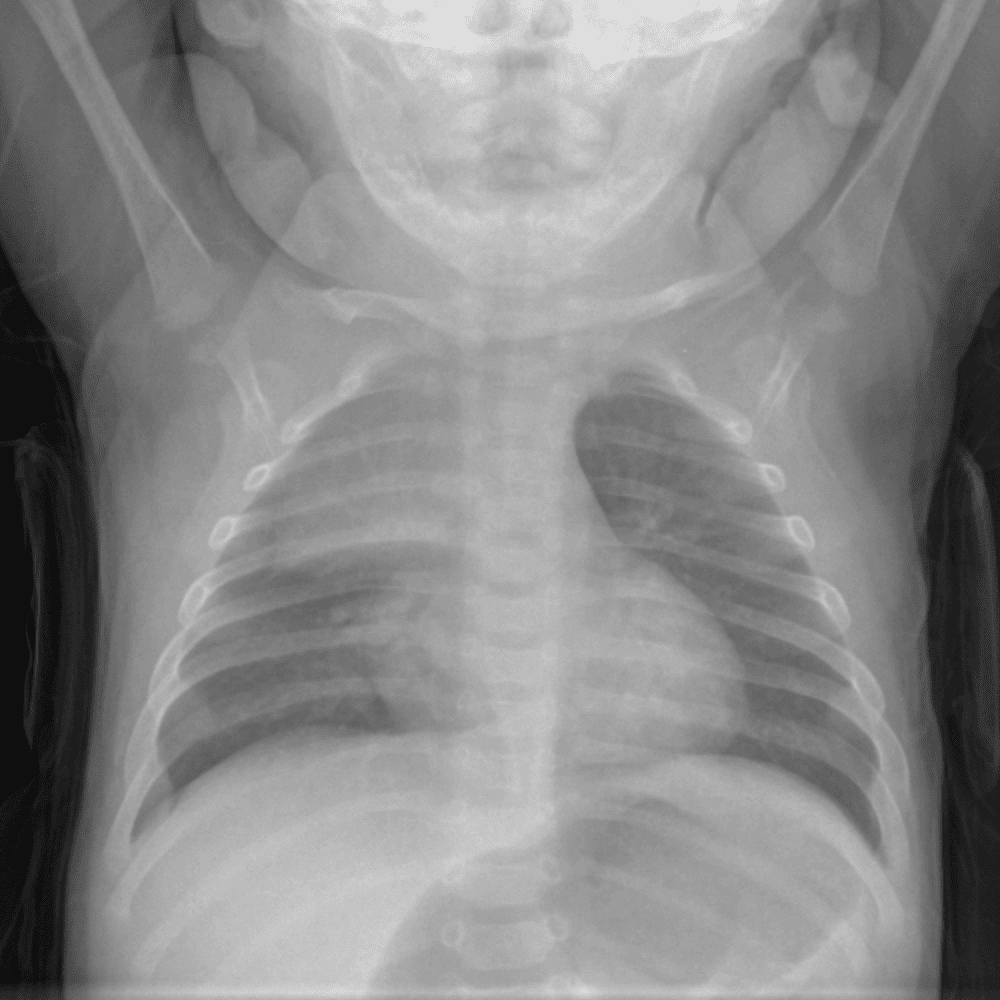

Peds Chest

Practice

Simulates call by including subtle or difficult cases and some normals.

50 cases